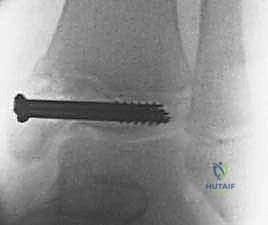

ثانياً: التدخل الجراحي (الرد المفتوح والتثبيت الداخلي - ORIF)

يصبح التدخل الجراحي ضرورة طبية لا مفر منها تحت إشراف الأستاذ الدكتور محمد هطيف في الحالات التالية:

* جميع كسور سالتر-هاريس من النوع الثالث والرابع إذا كان هناك تباعد أكثر من 2 ملم في السطح المفصلي.

* كسور تيلوكس والكسور ثلاثية المستويات ذات الانزياح الواضح.

3. إزالة الأنسجة المتداخلة والرد التشريحي (Debridement & Reduction)

هذه هي الخطوة الأهم. كما ذكرنا سابقاً، غالباً ما يتداخل السمحاق (Periosteum) داخل خط الكسر. يقوم الدكتور هطيف بإزالة هذا السمحاق المتداخل برفق، وتنظيف موقع الكسر من أي جلطات دموية أو شظايا عظمية صغيرة. بمجرد تنظيف الموقع، يتم إعادة القطع العظمية إلى مكانها الطبيعي بد